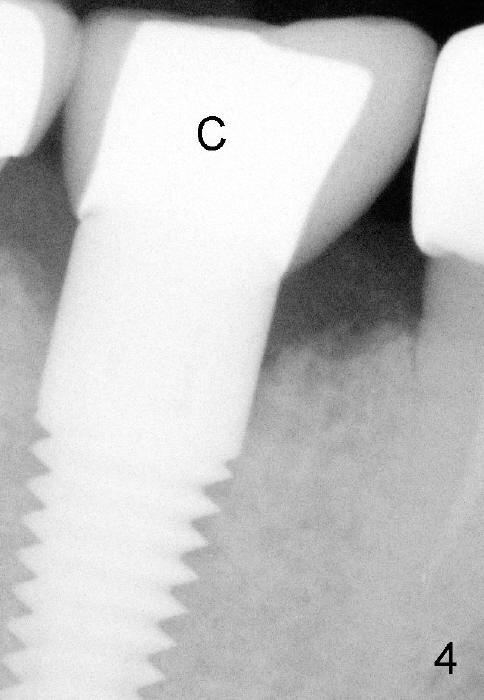

六十三岁台湾太太两年前右下第一磨牙准备做植牙,术前X光片显示缺牙区近中牙槽脊骨质好像有些特殊(图一箭头)。六乘十七毫米植牙(I)刚植入(图二,做了bone expansion),近中骨质好像又没有问题(箭头)。六个月后植牙近中骨质游离(图三箭头),除去骨片后,牙龈愈合,一个月后戴上牙冠(图四C),近中骨质仿佛没有异常。一年半后,病人突然回诊所,抱怨植牙周围流出臭味水,有些压痛。检查发现牙冠近中有个瘘道(图六箭头),下面好像有游离骨片,植牙牢靠,根尖片显示近中上部骨质稀疏(图五*),游离骨片(箭头)。翻开牙龈,除去相当大游离骨片,植牙粗糙面暴露(图七*,原有游离骨片所在地),除去炎性肉芽组织(+ +)后,植牙上部一两个螺纹暴露,箭头表示骨缺损边缘。反复用生理盐水冲洗,然后稀释四环素溶液冲洗,用探针和curet轻轻刮除植牙表面和螺纹菌斑,涂Straumann PrefGel,又用生理盐水冲洗,涂Endogain,植入Rocky Mountain Irradiated Allogenic Cancellous Bone and Marrow (图八*)。沐旭生医生认为植骨可能不管用,细菌很难清除,最好拔除植牙,植骨,然后再植牙。病人自己也意识到这个可能性,现在只有希望奇迹出现:缺损太大,不植骨身体可能无法修复。